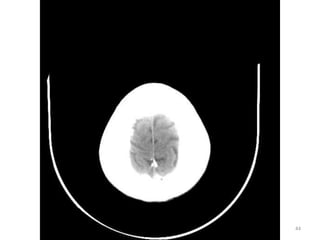

1. Fissura de Sylvios.

2. Foice do cérebro.

3. Terceiro ventrículo.

1. Corno Anterior do

Ventrículo lateral D.

2. Corpo caloso D.

4. Plexo coróide.